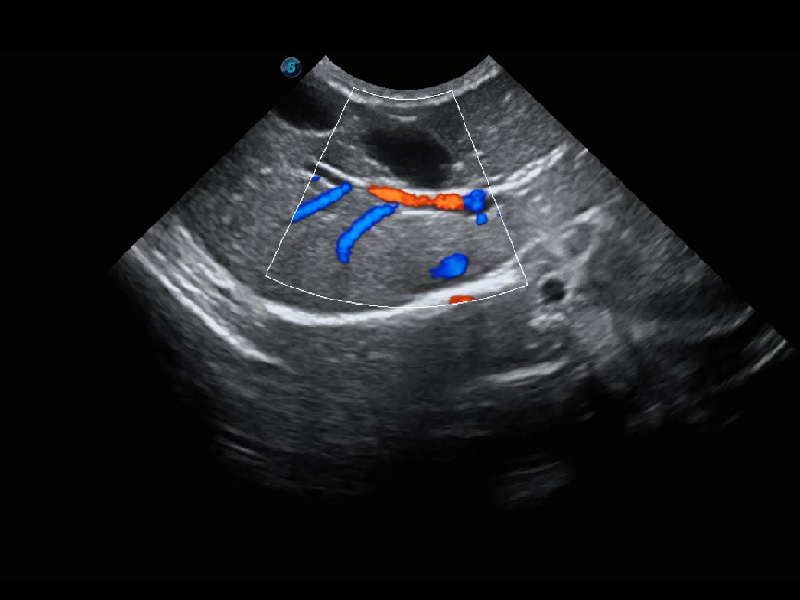

ProPet 60 作为一款高端台式动物超声设备,为动物医生的日常诊断提供了一系列贴合动物临床需求、解决临床实际问题的高级成像功能。凭借全系列高清探头,满足医生对腹部、心脏、生殖、浅表、肌骨等成像的所有需求,切实帮助您提升检查效率,提高诊断信心。

兽用彩色多普勒超声诊断系统